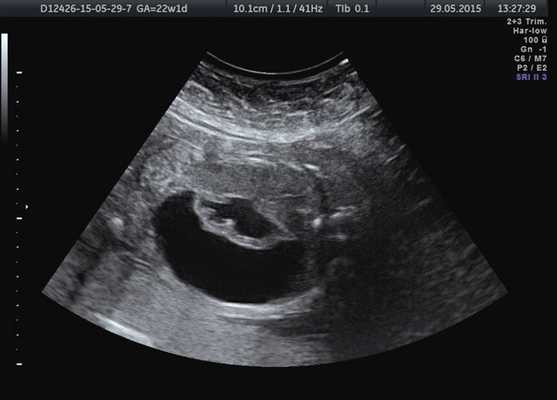

Лоханка правой почки была расширена до 13 мм, паренхима истончена и гиперэхогенна, кортикомедуллярная дифференцировка отсутствовала. При ЦДК кровоток в паренхиме не визуализировался. Вокруг правой почки по всему ее периметру определялось анэхогенное образование размером 56×20×26 мм (рис. 1, 2). Мочеточники с обеих сторон не визуализировались. Изменения левой почки отсутствовали. Мочевой пузырь был удовлетворительного наполнения и опорожнения. Оба надпочечника визуализировались.

Рис. 1. Образование вокруг правой почки плода.